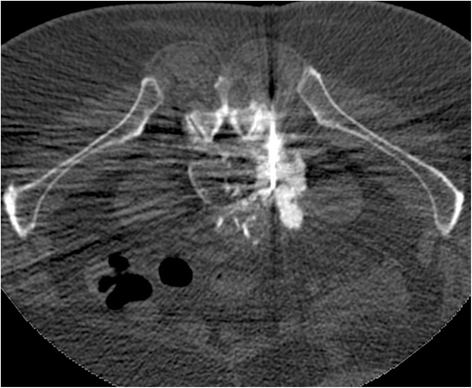

Case presentation: A 75 year-old patient was treated for a high grade transitional cell carcinoma of the bladder by surgery, chemotherapy and radiotherapy. Histology showed foci of bone metaplasia, both at the periphery of the tumor, and in a lymph node metastasis. 1 year later, a heterotopic bone formation was discovered in the right retroperitoneal space, near the lumbar spine, increasing rapidly in size during follow-up. Several imaging exams were performed (2 CT, 1 MRI, 1 Pet-CT), but in the absence of typical features of sarcoma, diagnosis remained unclear. Histology of a CT-guided percutaneous biopsy showed urothelial carcinoma and mature lamellar bone. Integration of these findings with the radiological description of extraosseous localization was consistent with a diagnosis of osseous metaplasia of an urothelial carcinoma metastasis. The absence of bone atypia in both the primary and metastases argues against sarcomatoid urothelial carcinoma with osteosarcomatous differentiation.

Conclusion: Osseous metaplasia of an urothelial carcinoma metastasis is unusual, and difficult to distinguish from radiotherapy induced sarcoma, or from sarcomatoid carcinoma. Rapid progression, sheathing of adjacent structures such as vessels (like inferior vena cava in our case) and nerves and bony feature of lymph node metastases necessitate histological confirmation and rapid treatment. Our case illustrates this disease and evaluates the imaging features. In addition we discuss the differential diagnosis of osseous retroperitoneal masses.